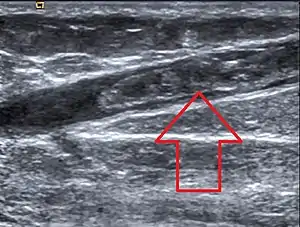

تشخیص بالینی از بارزترین مراحل تشخیص فلبیت بهشمار میرود و در ادامه به روشهای دیگر میتوان وجود تِرُمبُفلِبیت را تشخیص داد:

- اکوداپلر